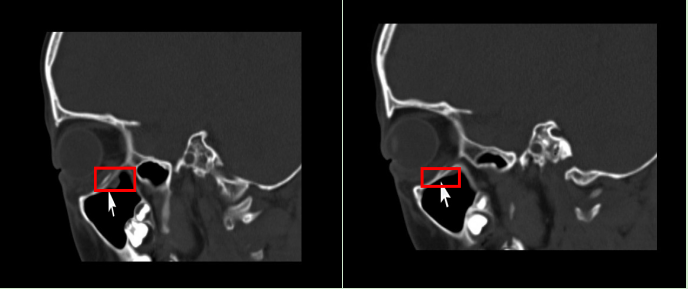

CT片显示,小杰的眼眶眶壁骨折,并且肌肉嵌到了骨缝里

小杰术前(左)术后(右)对比图,嵌入到骨缝里的肌肉功能术后已恢复

小杰的左眼眶下壁骨折,且有肌肉嵌顿在骨折的骨缝处,造成了眼球活动受限。这类手术视野狭窄,眶壁下血管丰富,神经密布,难度较大,要求医生有极高的手术技巧和丰富的手术经验。与此同时,在骨折后没有出血的情况下,越早接受手术对患者恢复越有利。经过详细的检查,小杰的手术被安排在5月19日下午,经过40多分钟的手术,许孝义教授团队成功为小杰修复了眶壁骨折,释放了嵌顿的肌肉。目前小杰正在医生的指导下进行进一步治疗,预后情况良好。